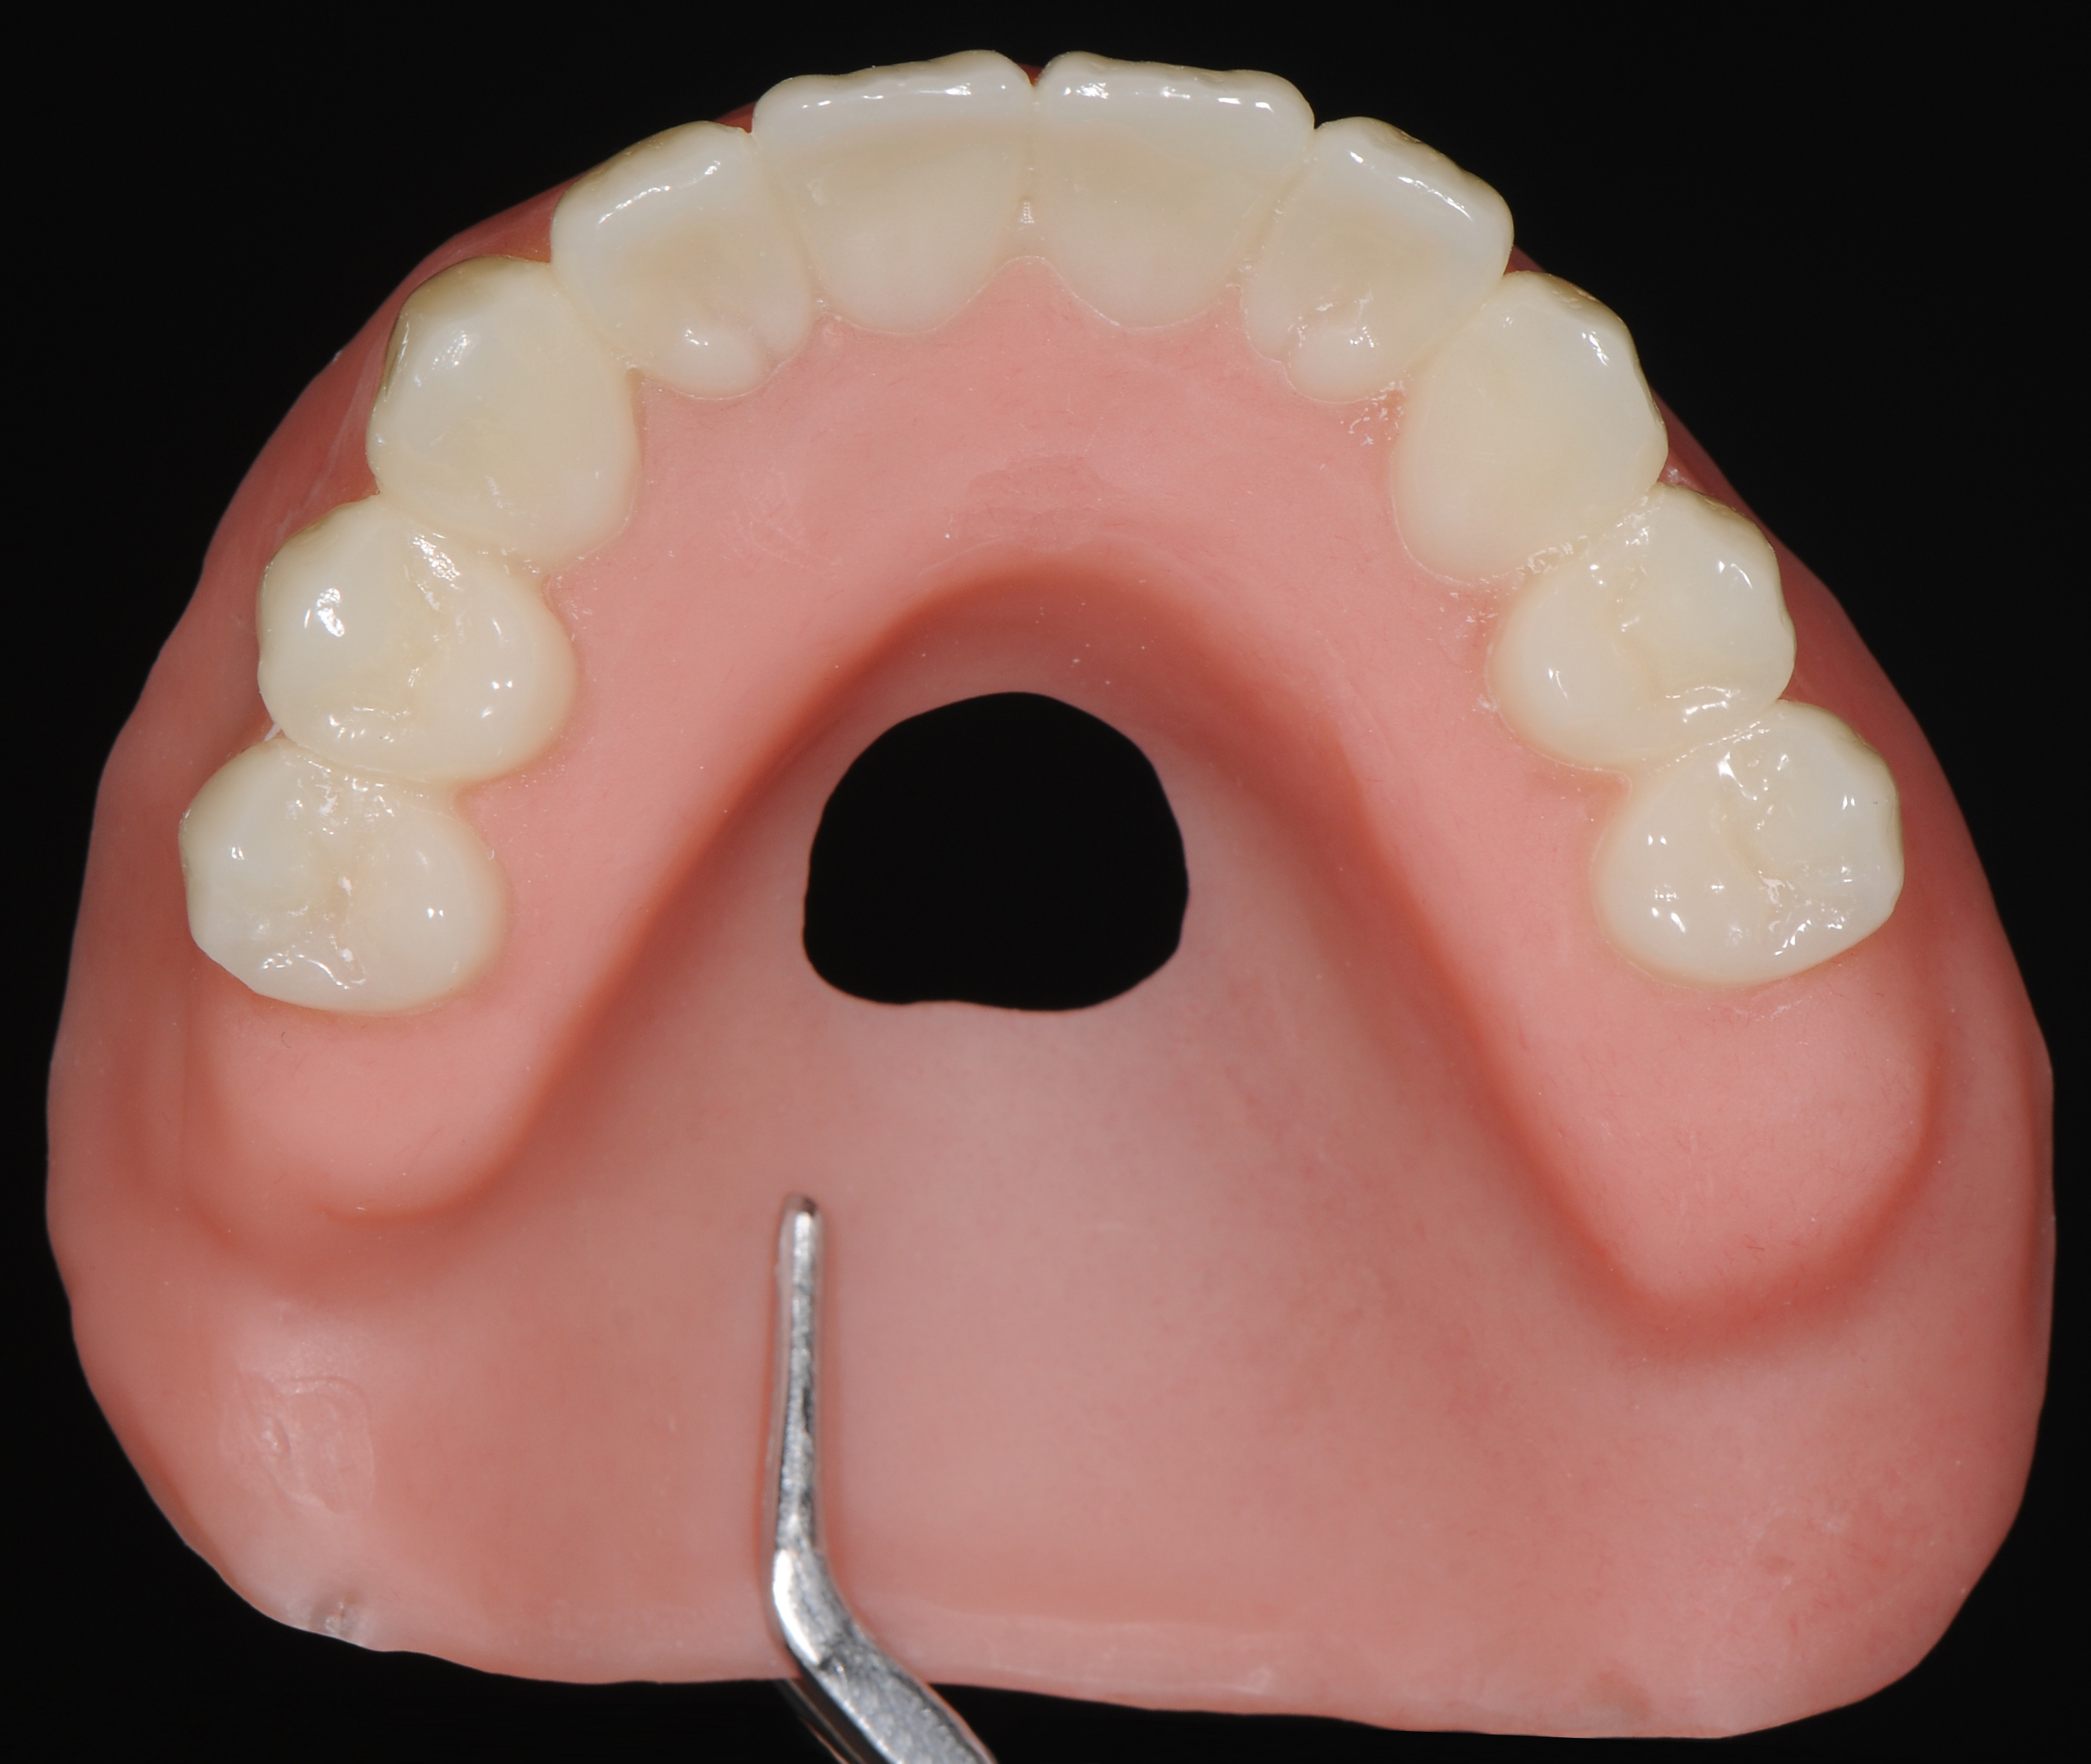

Перед проведением хирургического вмешательства были выполнены все этапы цифровой диагностики и планирования будущей работы. Изготовлены хирургический шаблон и акриловый базис будущего протеза, с ложем для последующего армирования (упрочнения) и индивидуализации временного протеза в день установки имплантатов на верхней челюсти. (рис. 5,6,7,8)

Хирургическое вмешательство проводилось в состояние медикаментозной седации в комбинации с местной анестезией. С использованием хирургического навигационного шаблона, пилотной фрезой была проведена разметка положения имплантатов на верхней челюсти. На начальном этапе без откидывания лоскутов. В боковых участках разрез десны проводился по вершине альвеолярного гребня, во фронтальном отделе выбран вестибулярный разрез с отступом около 2-3 мм от границы соединения прикреплённой десны к слизистой оболочки переходной складки для дальнейшего управляемого формирования зоны кератинизированной десны в области имплантатов. (рис 8,9,10)